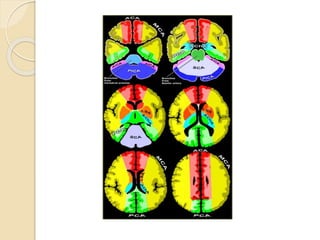

Cerebral Arterial Territory

 MCA-most of lateral hemisphere,

anterior and lateral temporal lobe,Basal

ganglia, insula,

 ACA-Inferomedial basal

ganglia,ventromedial frontal lobes,

anterior 2/3rd medial cerebral

hemispheres, 1 cm supero medial brain

convexity

 PCA-Thalami, midbrain, posterior 1/3of

medial hemisphere, occipital lobe,

postero medial temporal lobe

 Anterior Choroidal artery

branch of ICA supply part of the

hippocampus, the posterior limb of the

internal capsule

 Medial lenticulostriate arteries

They supply the anterior inferior parts of the

basal nuclei and the anterior limb of the

internal capsule.

 Lateral lenticulostriate arteries

They supply the superior part of the head and

the body of the caudate nucleus, most of the

globus pallidus and putamen and the

posterior limb of the internal capsule